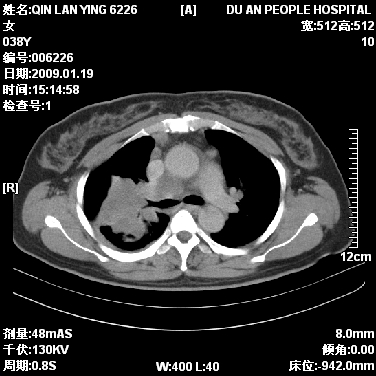

女,38岁,胸疼1个月。wbc:1万4

1)右肺中央型肺癌并右肺上叶阻塞性肺炎、节段性肺不张,纵隔淋巴结转移、右侧胸膜转移、肝脏转移。2)右侧胸腔少量积液。

1、右侧中央型肺癌并阻塞性肺不张,纵隔内、主动脉弓旁、右肺门淋巴结及肝脏转移可能性大,建议纤支镜进一步检查。

2、右侧胸腔积液。

本病例有几个容易诊断的地方:1、右肺上叶前段支气管闭塞,肺不张。2、淋巴结明显肿大。3、肝脏多个类圆形低密度影呈“牛眼征”改变,高度提示转移。

从影像学角度分析      右肺上叶中央型肺癌,并阻塞性不张、肺炎,纵隔淋巴结、膈顶淋巴结转移。

肝内两个大小不等低密度结节,内可见更低密度影,首先考虑肝内转移瘤,但联想到患者wbc1万4,建议楼主还是做个增强比较明确,除外肝脓肿的可能。